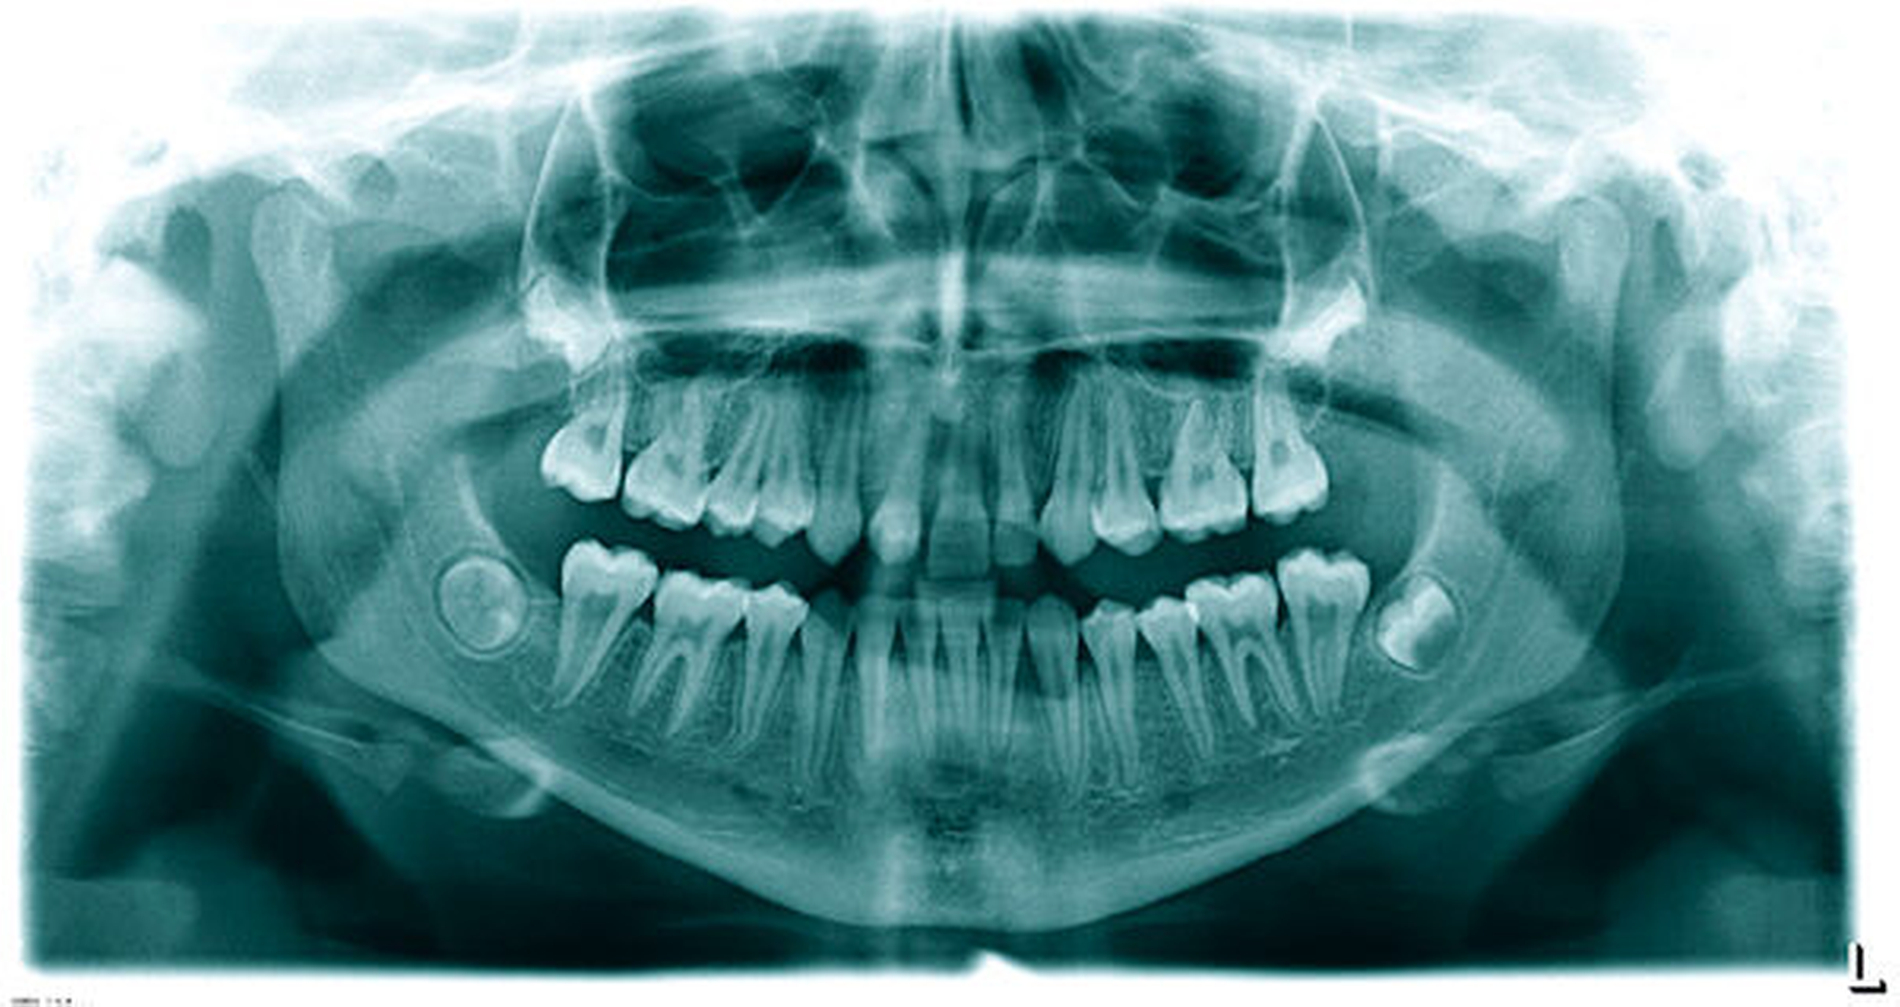

In der umfassenden Fortbildung „Die Einzelzahnlücke – Optionen der Versorgung“ (zm 4/2022 und zm 5/2022) wurde (neben den vielfältigen Therapieoptionen) nur marginal auf die Autotransplantation von Zähnen oder Zahnkeimen hingewiesen – mit der Anmerkung des sehr seltenen Vorkommens [Lapatki, 2022]. Dies trifft für Deutschland, nicht aber für die skandinavischen sowie weitere europäische Länder zu. Andreasen et al. [1990] berichten von 370 Prämolaren, die über einen Zeitraum von 13 Jahren hauptsächlich als Ersatz bei Aplasie transplantiert wurden. Kvint et al. [2010] beschreiben über 215 Autotransplantationen, bei denen 24 Prämolaren in die obere Schneidezahnregion transplantiert wurden – mit einer Erfolgsrate von 100 Prozent.

Die Häufigkeit für den Frontzahnverlust beträgt drei bis vier Prozent. Die Altersgipfel liegen zwischen dem achten und dem neunten sowie vom zwölften bis zum 14. Lebensjahr. Betroffene Zähne sind der mittlere und der seitliche Schneidezahn im Oberkiefer. Es besteht eine Korrelation der Häufigkeit zu den Zahnstellungsanomalien der vergrößerten sagittalen Schneidekantenstufe, dem schmalen Deckbiss mit protrudierten seitlichen Schneidezähnen und progen stehenden Einzelzähnen. Obwohl bei Avulsion die sofortige Reimplantation zum Erhalt des Zahnes führen kann, sind häufig Ankylosen des Parodonts und Wurzelresorptionen mit begrenzter Erhaltungswürdigkeit die Folgen. Eine fehlende Sensibilität, ein hoher Klopfschall und der röntgenologische Resorptionsnachweis sind diagnostische Anzeichen dafür.

Zeitpunkt und Auswahl des Transplantats

In der Regel sollte bei einem Frontzahnverlust im Oberkiefer ein Prämolar mit einer Wurzel verwendet werden. Die Wurzel einwurzeliger Prämolaren und deren Form sind in einer Schneidezahnalveole passfähiger und geeigneter für die parodontale Regeneration als ein Prämolar mit zwei Wurzeln. Der Prämolar sollte nach Möglichkeit aus dem Unterkiefer entnommen werden, da bei einem Misserfolg zwei Zähne innerhalb eines Kiefers fehlen würden. In der Regel wird die Extraktionslücke kieferorthopädisch mittels skelettaler Verankerung geschlossen. Zuvor ist die Anlage des dritten Molaren im betreffenden Quadranten zu prüfen, der nach kieferorthopädischer Einstellung mit dem zweiten Molaren des Oberkiefers okkludiert.

Das Wurzelwachstum des Transplantats sollte zum Zeitpunkt der Entnahme nicht mehr als zwei Drittel betragen. Dies kann eine operative Freilegung notwendig machen (Abb. 3).